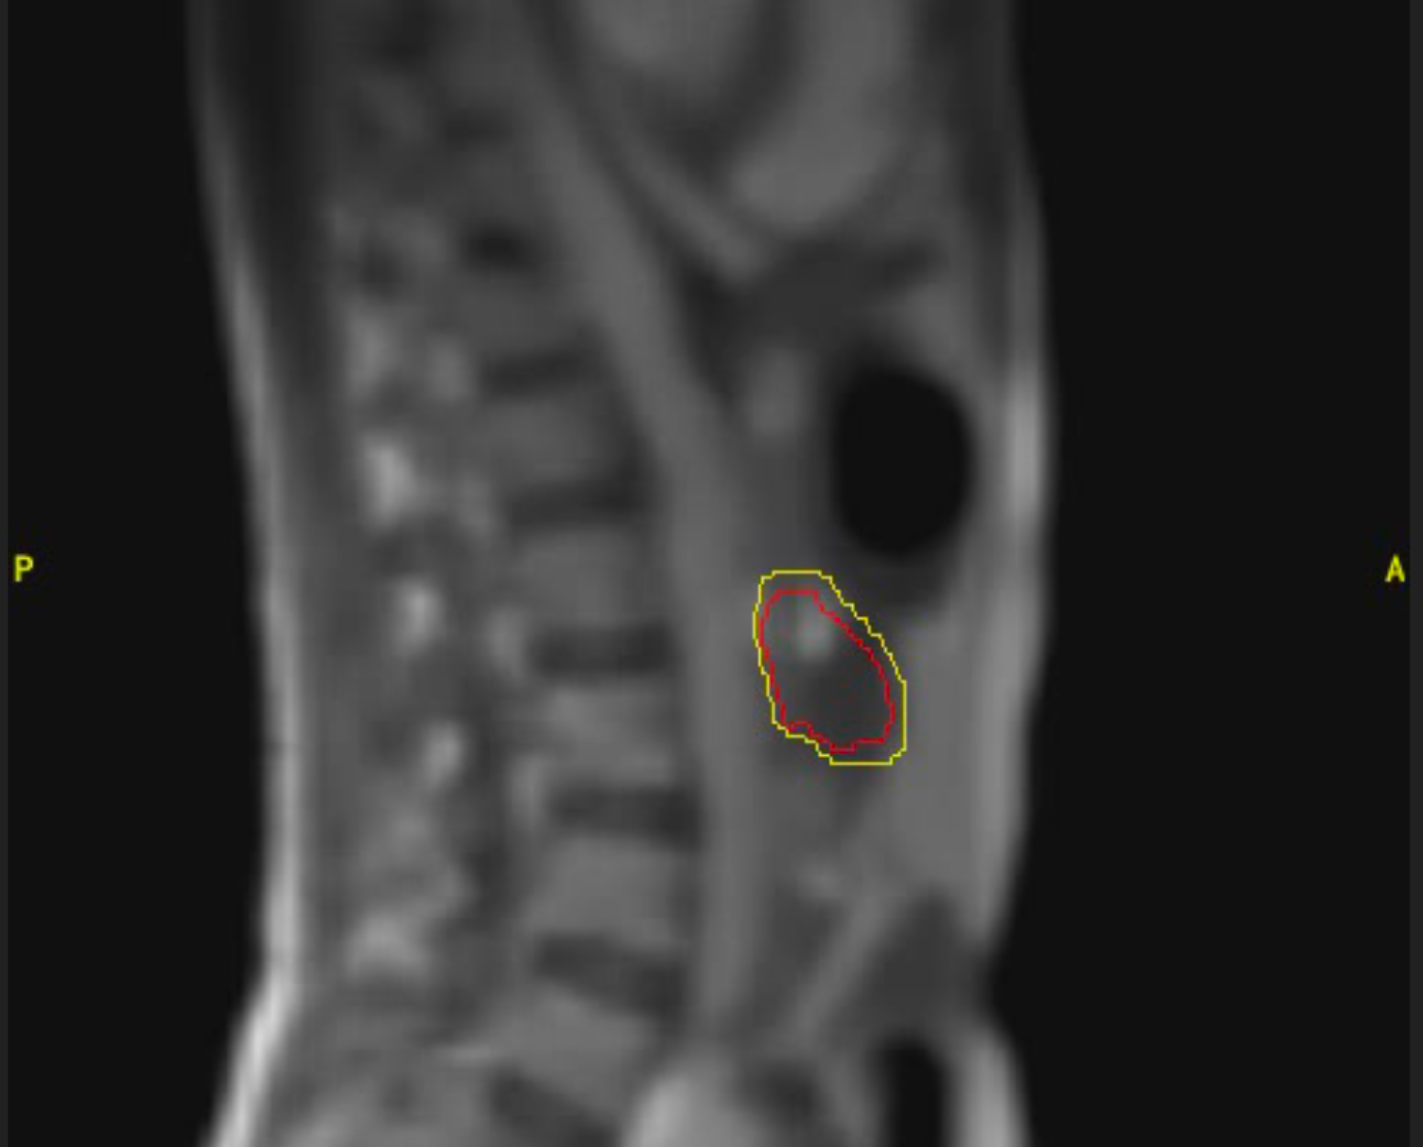

Cáncer de próstata

Varón de 85 años con diagnóstico de adenocarcinoma de próstata de bajo riesgo. Recibe tratamiento radioterápico con intención curativa en Acelerador Lineal con Resonancia (MRIdian): 5 fracciones en 5 días. Buena tolerancia, no efectos adversos destacables salvo ligero escozor al orinar autolimitado durante una semana.

Imagen 1

Imagen 2

Imagen 3